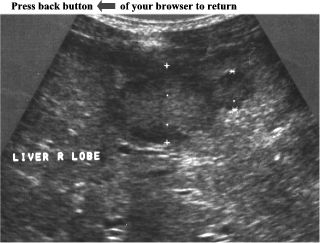

CASE 6:

Ultrasound examination of the right liver lobe revealed two adjacent, hypoechoic, well defined masses. The size of the masses were 2,6cm and 1,3cm respectively. Both masses had hypoechoic halo around which made the masses easily distinguishable from surrounding liver parenchyma. The rest of the liver parenchyma was normal.

Hepatic Metastases